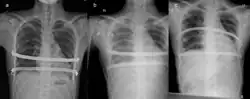

Iatrogenic hemothorax resulting from the Nuss procedure. A showing no hemothorax, b showing hemothorax, and c showing resolution after treatment.

Other complications which may occur include hemothorax, pleural effusion, pericarditis, wound infection and pneumonia and acquired scoliosis.[6]: 340  Vigorous incentive spirometry is used to prevent pneumonia.[6]: 341  Some patients are allergic to one of the components of stainless steel.[6]: 341  As a result, allergy testing is now routinely done prior to surgery. In the event of an allergy, a titanium bar will be used.